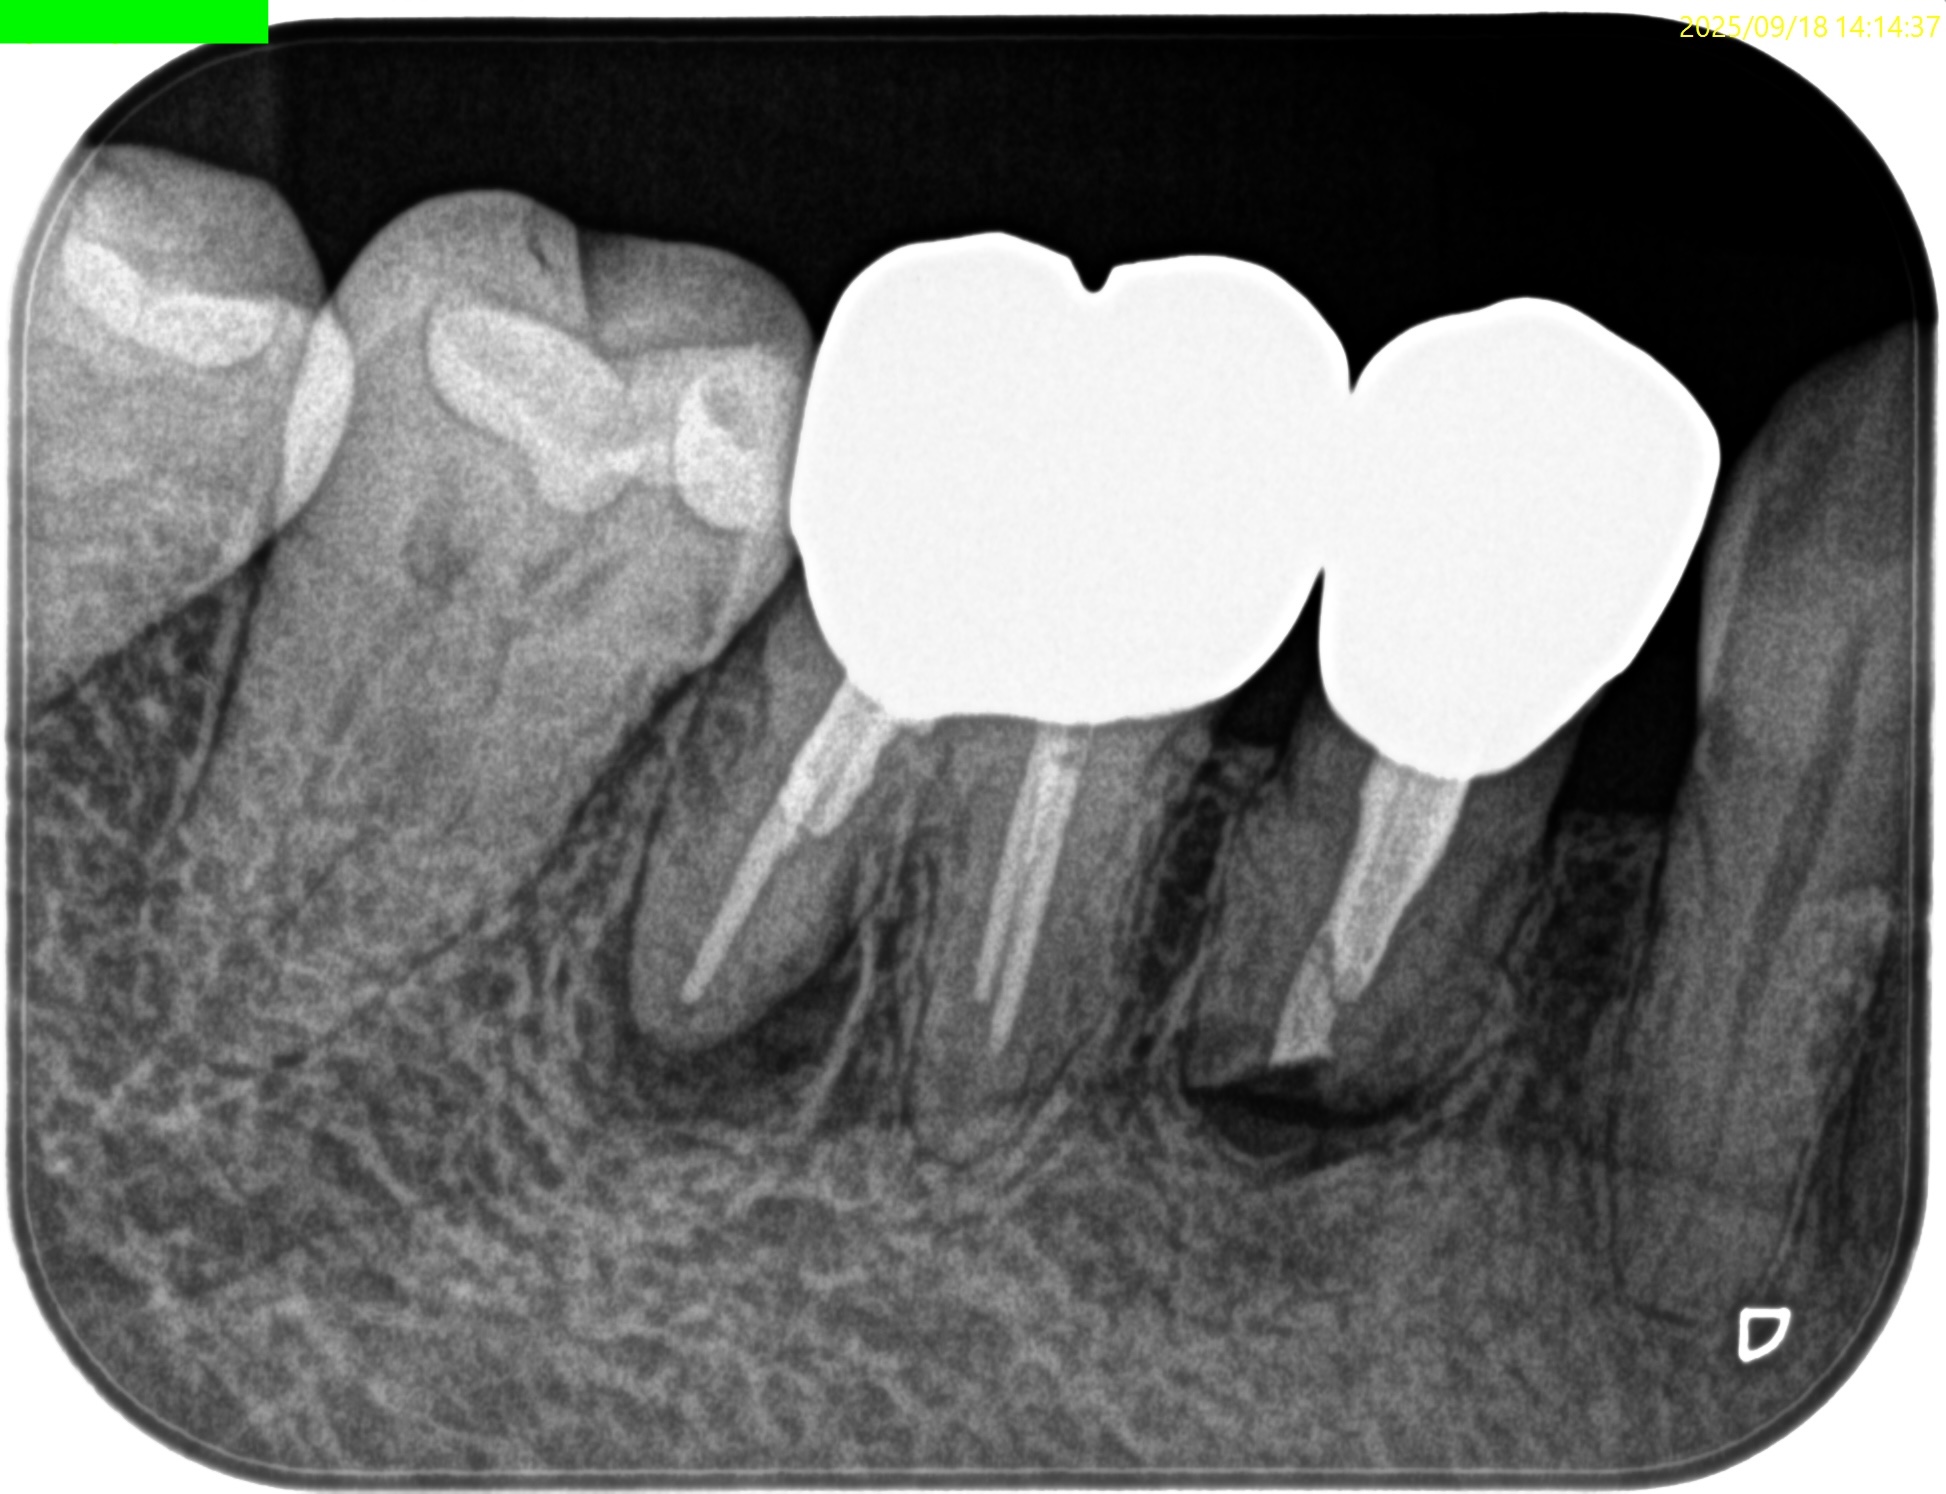

という中、外科後5年で歯茎が腫れて痛いと連絡がある。

#30 DはApicoectomyであり、先日の記事通りである。

では#29はどうなのか?といえば、

VRFも疑われるような状況である。